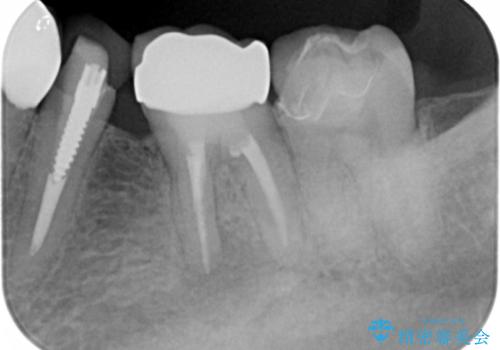

左下の奥歯(左下6)の劣化した白い被せ物と金属の土台を除去し、セラミッククラウンによる補綴治療を行いました。

セラミッククラウンの天然歯のような自然な仕上がりと咬み心地に喜んで頂けました。

クラウンの種類:オールセラミッククラウン スタンダード